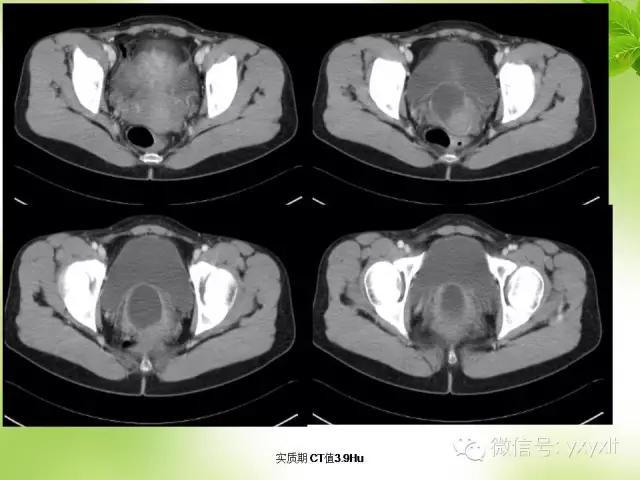

CT:囊肿表现为单房或多房的薄壁水样低密度病灶薄壁囊性肿块,边缘清楚光整。增强扫描未见强化。